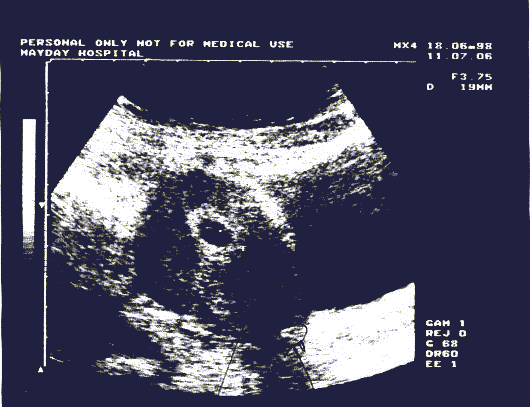

MRI scan showing a clear foreign object

in the colon / base of spine area.

Not one medical person in Britain will admit this.